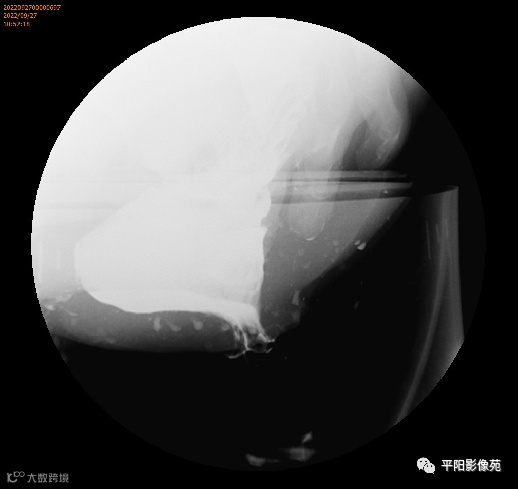

排粪造影

手术

排便造影钡(x射线)排便造影或排便直肠造影是诊断排便障碍的公认临床

工具

。

钡排粪造影实时评估直肠壁形态、盆底运动和排空。